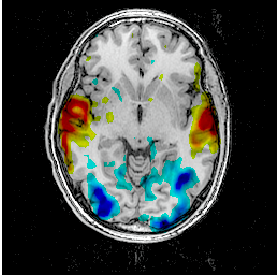

Fusion between an anatomical volume and an activation map

Load:

T1 MRI:

data_for_anatomist/subject01/subject01.niiActivation map:

data_for_anatomist/subject01/Audio-Video_T_map.nii

Fusion the 2 images. Note that they are not well superimposed because they are not in the same referential. But they are in Nifti format and contain information about a transformation to the referential Talairach-MNI Template-SPM.

For each volume, right-click Referential => Load information from file header.

Look at the fusion, the 2 images are now well superimposed.

Change the point of view by changing the referential of the window: click on the colored bar at the top of the window and choose Talairach-MNI Template-SPM. Notice the change of orientation.

Fusion between an activation map and a T1 MRI¶